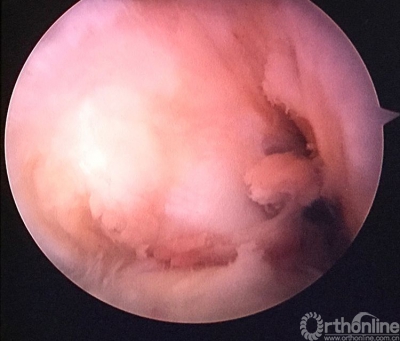

关节镜检查见重建的韧带已经消失。

原来重建的ACL胫骨隧道内口偏前(等离子刀头所指处)。

现等离子刀头所指处应该为正确的内口定位,原内口与此处相距较远。

现等离子刀头所指处为外侧半月板前角游离缘。左下方2个等离子刀烧灼处为原内口及准备返修的内口。